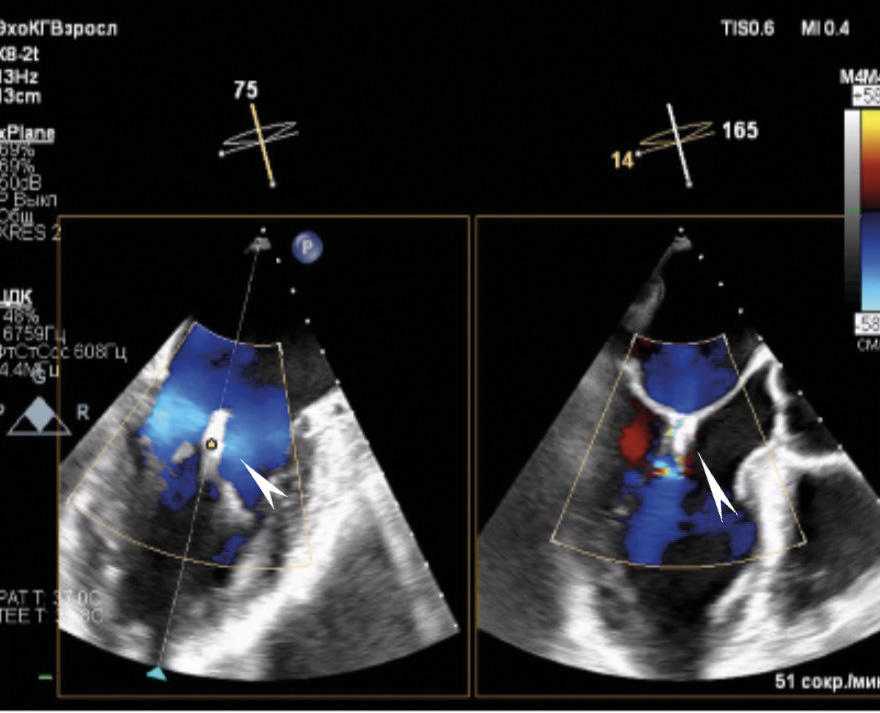

По результатам ЧП ЭхоКГ после вмешательства: в проекции МК визуализируется 1 клипса, митральная регургитация до 1-й степени (площадь струи регургитации 4,5 см2), величина коаптации менее 3 мм. Площадь отверстия МК – 4,7 см2. Кольцо МК = 3,45/3,8 см. Средний диастолический градиент на МК – 2,1 мм рт. ст. Место имплантации клипсы без особенностей. Количество струй регургитации – 1, тип регургитации – эксцентрический, распространяющийся вдоль межпредсердной перегородки. В просвете УЛП визуализируется плотно фиксированный окклюдер. Периферического кровотока по краям окклюдера не выявлено. В месте пункции межпредсердной перегородки визуализируется лево-правый сброс до 3 мм. Данные ЧП ЭхоКГ после вмешательства приведены на рис. 3–5.

Рис. 4. В режиме цветного доплеровского картирования патологического сброса и краевых потоков в проекции установленного окклюдера в ушке левого предсердия не выявлено (окклюдер указан стрелкой)

Рис. 5. В проекции митрального клапана лоцируется гиперэхогенная линейная структура – клипса (указано стрелкой). В режиме цветного доплеровского картирования регургитация до 1-й степени, средний градиент на митральном клапане 2 мм рт. ст.